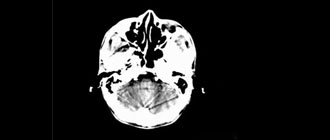

CT圖像故障分析與判斷

CT圖像異常的故障比較多見,表現(xiàn)的形態(tài)也各不相同,如雪花點、螺紋影、同心圓、條紋影等,無論是機械故障、電器故障、還是軟件故障,都可能反映在圖像上表現(xiàn)為異常偽影。

CT偽影分析

CT圖像上的偽影是指在成像過程中產(chǎn)生與被掃描組織結(jié)構(gòu)無關(guān)的異常影像。分析和判斷偽影的形成原因,認識偽影的各種特征。才能迅速排除問題,最大限度的減少因偽影。